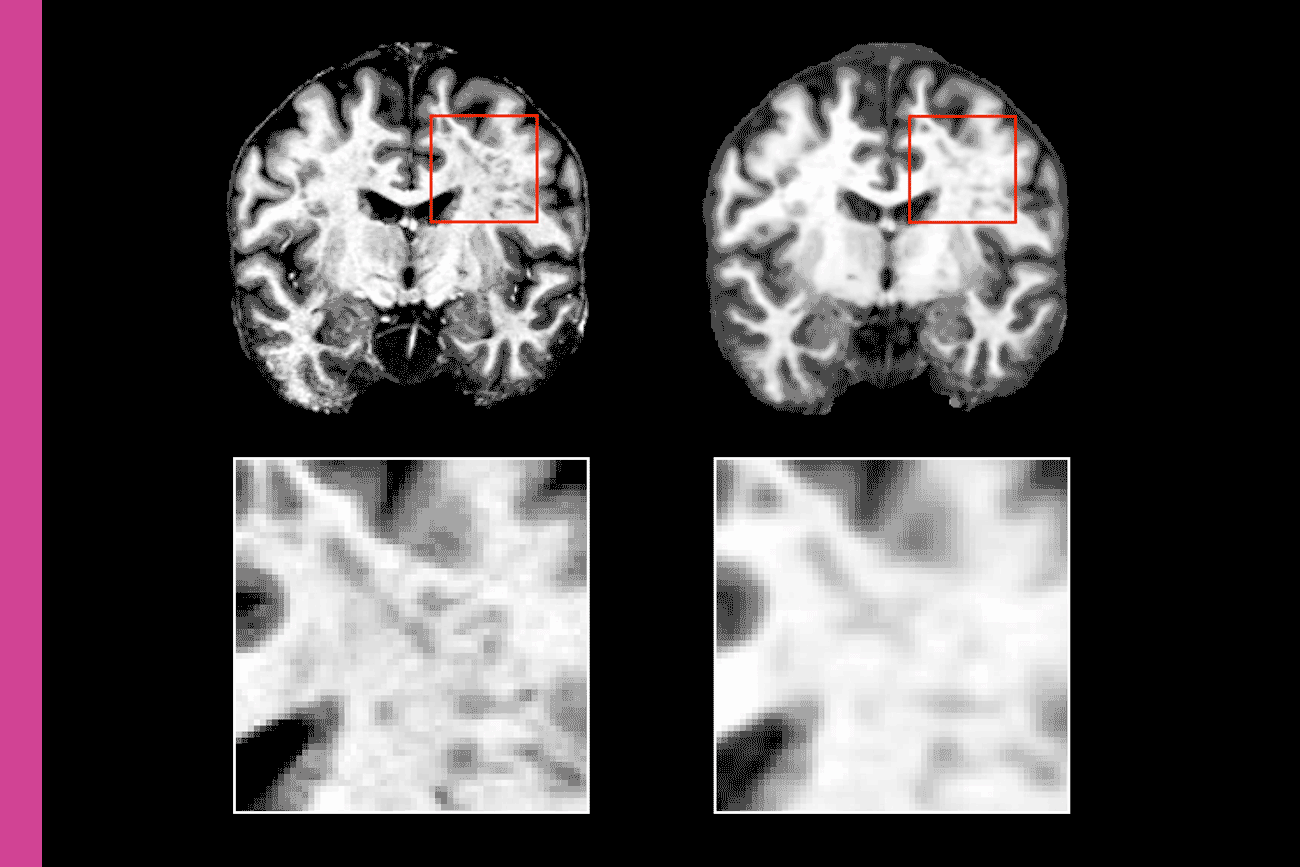

UCSF assistant professor of Neurology Reza Abbasi-Asl, Ph.D., led a team that used a form of AI to enhance the resolution of standard MRIs featuring traumatic brain injuries. The technique dramatically improved 3T MRI images, putting them roughly on par with 7T images, while outperforming other types of AI-enhanced MRIs.

Abbasi-Asl and team constructed small, anonymous databases of pairs of traumatic brain injury MRIs. Each pair contained MRIs of the same injury: one low-resolution, 3T version, and another high-resolution, 7T version. The team created machine learning models that connect bits of information based on data patterns to boost low-resolution images before comparing them to their high-resolution partners.

The outcomes of these models identified patterns and features that were hard to detect for the human eye in 3T MRIs, using them to understand how to improve image quality — boosting specific details while minimizing “noise” like grainy specks.